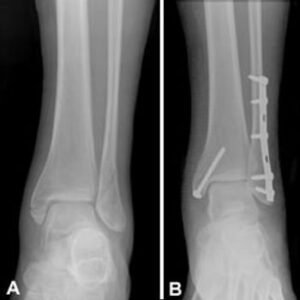

- Joint fusion using plates, screws, or rods

X-ray or CT/MRI

What imaging tests are needed before the surgery?

X-rays, CT scans, or MRI are used to understand the damage and plan the surgery with precision.

What materials are used for fixation?

Plates, screws, rods, or bone grafts may be used to support the bones while they fuse.